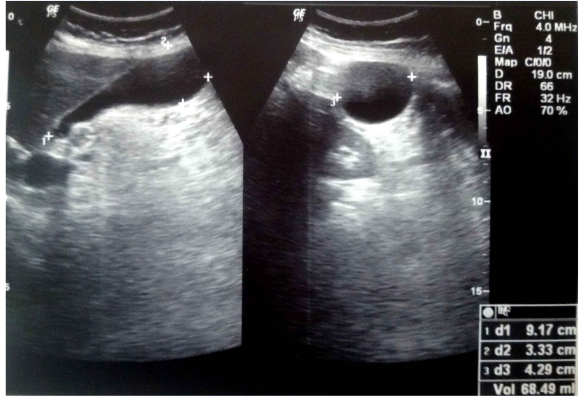

A 14-years-old vegetarian female child presented with mild to moderate pain in whole of the abdomen for one year. Pain was not related to the meal. There was history of few episodes of vomiting after attack of moderate to severe pain in last three months. She attained her menarche at 12years of age. She consulted to pediatric surgeon who gave her antispasmodic and antacids. Ultrasonography (USG) abdomen (Figure 6) showed well distended gallbladder with normal wall thickness but few small concretions and sludge in the lumen. The pediatric surgeon advised her laparoscopic cholecystectomy. She consulted me to the second opinion for the same ailment. The systemic and local examinations were within normal limits. The blood biochemistry and serology were also within normal limit. Because there was no obvious complication and problem, patient was given a chance for the conservative management before the definitive treatment i.e. Cholecystectomy. Patient was given OmlivTM one tablet twice daily and Tablet Drotaverine 20mg SOS for 45days. The follow-up USG (Figure 7) revealed normally distended gallbladder with normal wall thickness and clear lumen. It was concluded that the OmlivTM can clear the gallbladder sludge and is also effective for the symptomatic improvement of the patient.

Figure 6 Case No. 3 [Pre-treatment ultrasonography scan showing biliary sludge].

Figure 7 Case No. 3 [Post-treatment ultrasonography scan showing clear gallbladder lumen].